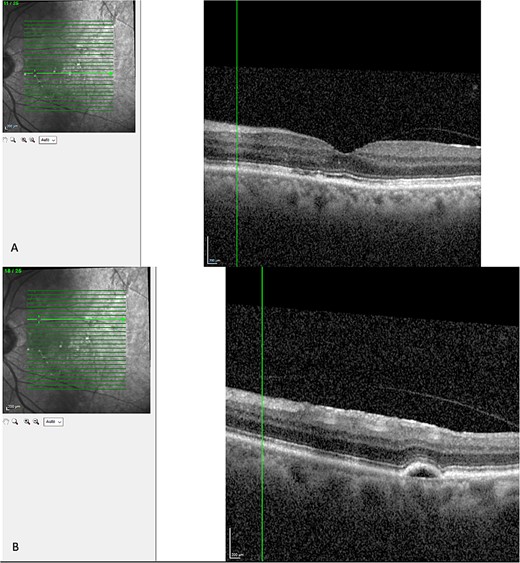

Optical coherence tomography (OCT) demonstrated an atrophied right macular. Whilst the left eye showed a thickened choroid, multiple pigment epithelial detachments (PED), subretinal fluid and intraretinal fluid nasally. This is shown in Figs 2 and 3.

(A) OCT of left eye – IRF and SRF with serous retinal detachment. Choroidal thickness = 454 μm.

The diagnosis of CSCR was made by the patient’s ophthalmologist, meeting diagnostic criteria as seen in Table 1. The patient meets major criteria with an OCT showing serous retinal detachment, and RPE alterations seen in Figs 2 and 3, respectively. Figure 2 displays a subfoveal choroidal thickness of 454 μm meeting the minor criteria.